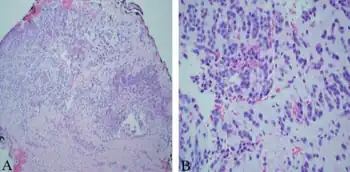

| a,b)Monomorphic round tumor cells with minimal cytoplasm in loose myxoid background, consistent with extraskeletal myxoid chondrosarcoma. | |

EMC shows the smallest morphological variation between the tumors among all myxoid soft tissue neoplasms. The myxoid matrix has a fibrous structure that is different from the grainy appearance of most other myxoid lesions. It is stained with magenta in the air-dried samples. Among all myxoid tumors, EMC has the least vascular structures. Chondroblast-like lacunas may be formed, but no differentiation of hyaline cartilago has been described.

Smears contain plump spindle-shaped or oval tumor cells arranged in a lacelike pattern of loosely cohesive cords and nests. The malignant cells are uniform and lack nuclear pleomorphism. The nuclei have round or oval shape and are hyperchromatic with finely stippled chromatin. The nucleolus is small and inconspicuous. Nuclear clefts and grooves are common and the cytoplasm is homogeneous, scanty to moderately abundant, and often appears wispy and tapered, with well-defined borders of cells.